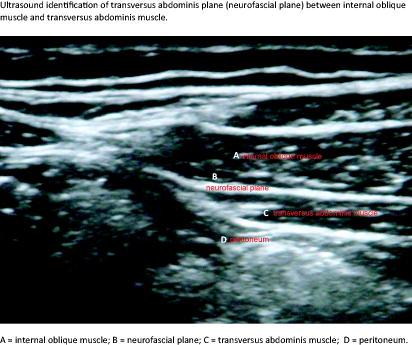

The transversus abdominis plane (TAP) block is a regional block used for postoperative pain treatment after abdominal surgery. The anterolateral abdominal wall is innervated by peripheral nerves of spinal roots T6-L1. The purpose of the TAP block is to anaesthetise these sensory nerves by injecting 20-40 ml of local anaesthetics into the neurofascial plane between the internal oblique and the transversus abdominis muscles.

The two clinical investigators used the same TAP block approach. The insertion site, 5-8 cm lateral to the sagittal plane at the level of the umbilicus, was identified and correct injection into the neurofascial plane between the internal oblique and the transversus abdominis muscles, lateral to the rectus sheath, was visualised using US, GE Medical Systems Logiqe. For facilitation of the TAP-block, 4 ml of lidocaine 1% was administered subcutaneously at the insertion site. Afterwards, the TAP-block was performed under US-guidance in the awake patient, with injection of 20 ml ropivacaine 0.5% bilaterally via Braun Stimuplex needles. We chose a common clinical method, i.e. assessment of pinprick and cold sensitivity. The patient was asked to register a prick or coldness, respectively, on the upper extremity. Sensory change was then assessed bilaterally in the midclavicular line, starting above dermatome T4, moving caudally to dermatome L4. Pinprick was tested with a blunt needle with minimal skin deformation and cold with cold disinfectant swabs at 10, 20 and 30 minutes after ropivacaine injection. The patient notified the examiner as soon as he perceived a change in sensation. Variability of pressure was further limited as only two investigators were involved. As testing with cold was carried out with wet disinfectant swabs, the evaporation during the test was minimal. We used a standard dermatome chart where the xiphoid process corresponded to T6, umbilicus to T10 and the inguinal ligament to L1. Thereafter patients were anaesthetised and operated as scheduled. Postoperatively, the patients followed routine care and were not investigated further.